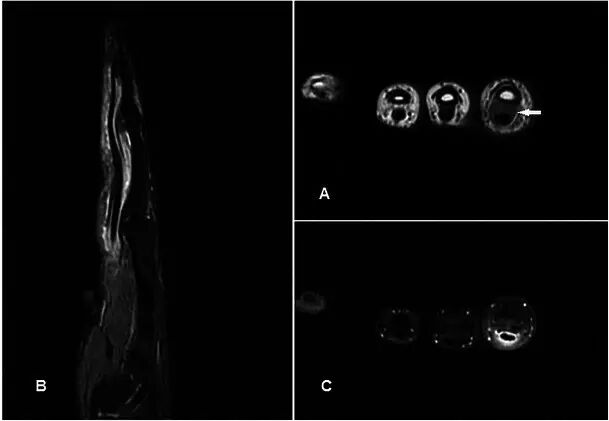

脂肪纤维性错构瘤Lipofibromatous hamartoma 脂肪纤维性错构瘤是罕见的良性肿瘤,通常涉及手腕的正中神经[23]。它通常呈现为逐渐扩大块状或有压迫神经的症状,大部分发生在30岁之前。过量的纤维脂肪组织沿着神经束周围的神经束周围的神经鞘增殖。 这给予病变其在MR成像上的病理学外观。MR通常显示出表示具有“serpinginous”,“意大利面”或“电缆”样外观的增大的神经的梭形肿胀,代表由脂肪组织包围的低信号轴突[24,25](图7)。管理一般是保守治疗,因为手术切除几乎总是伴有神经系统的损伤[26]。

图7.在45岁男性纤维脂肪性错构瘤,在左手的第一网状空间中具有1年的持续时间。 (a)T1w序列显示在第一网状空间内的良好外观的高信号皮下分叶损伤,具有类似于“类似于意大利面”外观的曲线低信号结构(箭头)。 (b)在T2w-FS序列上,损伤显示均匀的信号丢失,表明主要是脂肪损伤,而曲线结构通过损伤中心出现高信号。 (c)这些曲线结构显示增强(箭头)。 发现这些代表术中的病变的神经血管组分。 损伤的其余部分没有显示显着的增强